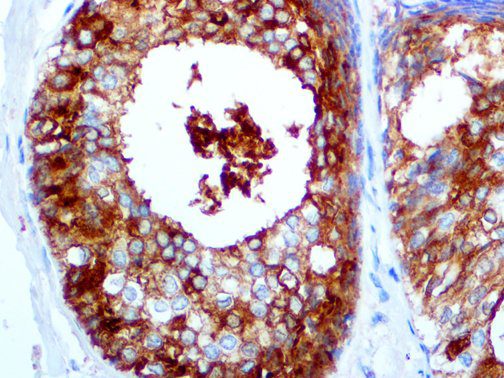

It is the ICU physician who is most likely to witness one of the deadliest manifestations of the abnormal immunological response, the cytokine storm syndrome (CSS). This response is also referred to by some as the cytokine release syndrome (CRS). CSS is characterized by continuous activation and expansion of macrophage and lymphocyte populations, which secrete large amounts of cytokines, causing the cytokine storm. This massive cytokine release is akin to hemophagocytic lymphohistiocytosis (HLH) disease, a syndrome characterized by initial unchecked and persistent activation of cytotoxic T lymphocytes and NK cells.

Clinical and laboratory manifestations of HLH include fever, enlarged liver and/or spleen, neurologic dysfunction, coagulopathy, liver dysfunction, cytopenias (i.e., low levels of erythrocytes, leukocytes, and/or platelets), hypertriglyceridemia, hyperferritinemia, hemophagocytosis, and eventually diminished NK cell activity as the immune system becomes progressively paralyzed. HLH can be familial (primary HLH) or secondary to another disease process (sHLH), such as rheumatic disease, in which it is referred to as macrophage activation syndrome (MAS, characterized by elevated ferritin).